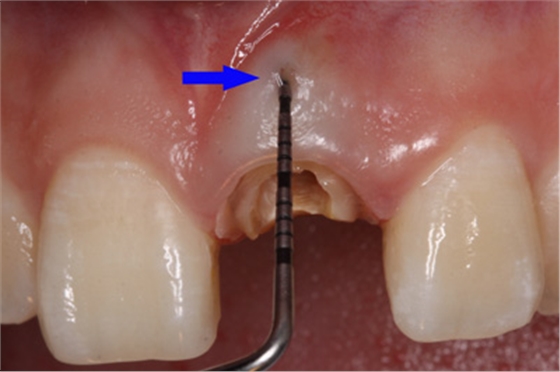

因此,臨床上正確判斷穿孔的發(fā)生十分必要。穿孔出現(xiàn)的主要表現(xiàn)為:拔凈牙髓后,根管內(nèi)出血明顯,吸潮紙尖中部有血跡,尖端干凈;x線診斷絲從根管壁穿出;根管長度測(cè)量儀在根管銼未到工作長度時(shí)顯示超出根尖孔;顯微鏡下能看到明顯的穿孔部位和牙周軟組織的粉紅顏色,或陳舊的壞死樣軟組織。

唇側(cè)出現(xiàn)瘺管